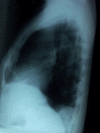

With CT (computed tomography) chest gaining more importance as a diagnostic tool, chest X-ray especially the lateral view is taken less commonly nowadays. Besides CT chest is also proven to be superior to chest X-ray in patients with major blunt trauma. We are presenting a 68-year old male who was partially treated from outside for a left sided pneumonia. He came to our hospital because of persisting chest pain. Chest X-ray, frontal view (postero-anterior) was almost normal except for a mild opacity in the left lower zone. CT scan of the chest revealed a fluid collection posteriorly enclosed within enhancing pleura. Chest X-ray, left lateral view showed a corresponding posterior pleural based opacity. We are presenting this case to highlight the importance of the lateral view of the chest X-ray. In selected cases there is still a role for the lateral view. With the three dimensional visualization provided by the CT, the lateral view of the chest may be easier to understand. Consequent to the initial diagnosis by CT further follow up can be done with the chest X-ray. In a limited way this mitigates unnecessary expenditure and more importantly prevents the patient from exposure to harmful radiation in the form of repeated CT.